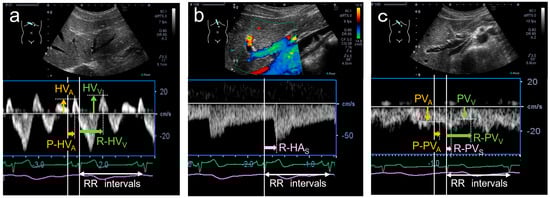

| HVA | A-wave in hepatic venous flow |

| HVV | V-wave in hepatic venous flow |

| P-HVA | Time from the P-wave to the A-wave in hepatic venous flow |

| R-HVV | Time from the R-wave to the V-wave in hepatic venous flow |

| R-HAS | Time from the R-wave to peak systolic velocity in hepatic arterial flow |

| PVA | Atrial-systolic descent in portal venous flow |

| PVV | Ventricular-systolic descent in portal venous flow |

| PVS | Systolic forward flow in portal venous flow |

| P-PVA | Time from the P-wave to atrial-systolic descent in portal venous flow |

| R-PVV | Time from the R-wave to ventricular systolic descent in portal venous flow |

| P-PVA vs. P-HVA | 23 | 0.17 ± 0.08 | 0.14 ± 0.03 | 0.109 |

| R-PVV vs. R-HVV | 41 | 0.42 ± 0.09 | 0.43 ± 0.06 | 0.246 |

| R-PVS vs. R-HAS | 34 | 0.20 ± 0.07 | 0.24 ± 0.06 | 0.048 |